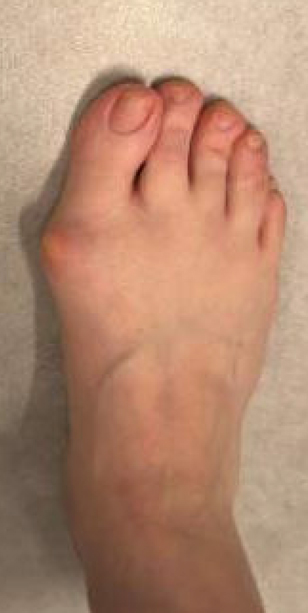

TOTAL ANKLE REPLACEMENT :: ORIF CALCANEUS :: ORIF ANKLE FRACTURE DISLOCATION :: COMPLEX BUNION AND LESSER TOE CORRECTION :: TALUS FRACTURE -1 :: TALUS FRACTURE -2 :: LISFRANC REPAIR :: COMPLEX TRIPLE ARTHRODESIS 1 :: COMPLEX TRIPLE ARTHRODESIS 2 :: MINIMALLY INVASIVE BUNION REPAIR 1 :: MINIMALLY INVASIVE BUNION REPAIR 2 :: ARTHROSCOPIC CARTILAGE REPAIR :: TENEX SPUR DEBRIDEMENT :: Haglunds Debridement and Achilles Repair